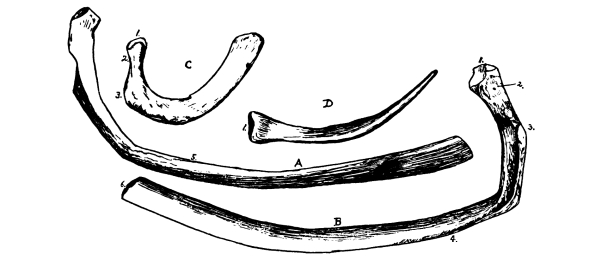

The Sternum, 97—The Ribs, 97—Costal Cartilages, 98—Muscles of the Chest, 98—Diaphragm, 98—Mammary Glands, 100. |